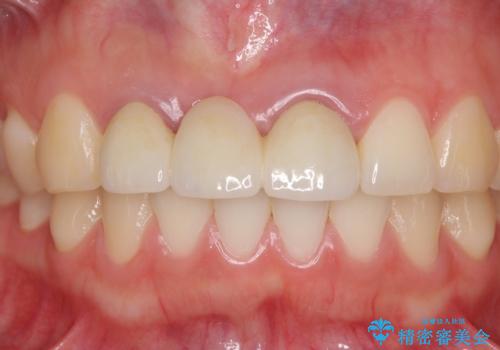

歯肉から血が 前歯のオールセラミックブリッジの再製作

- 他院で装着したばかりの前歯のブリッジが気に入らず、作り替えを希望して来院された患者様です。

前院では、土台の金属を除去することは不可能であると言われたとのことでした。金属の土台が残っているとセラミックにグレーの金属色が透けて見えてしまうため、拡大鏡やマイクロスコープを用いて丁寧に除去し、天然歯の色に近いファイバーコアを植立することとしました。

また、歯とクラウンの境目が合っていない部分が多く、歯肉からの出血が認められました。

金属色の透けた感じも歯肉からの出血もなくなり、自然な仕上がりの前歯となったので、患者様には大変満足していただきました。